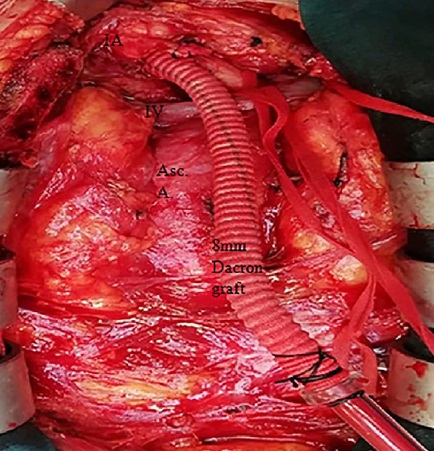

General anesthesia was used in all patients. Arterial blood pressure was monitored for both arms (radial or brachial arteries). After a standard median sternotomy, the innominate vein was encircled with an umbilical tape and retracted to expose the arcus aorta and its major branches. The IA was exposed and dissected to the bifurcation. An umbilical tape was passed around it to allow caudal retraction. After systemic heparinization (3 mg/kg or 300 IU/kg to achieve activated coagulation time > 480 seconds), a partially side clamp was applied to the distal IA. In cases of small size IA, complete flow occlusion of the IA using two vascular clamps was performed. The right radial artery pressure was measured to evaluate the adequate distal perfusion to the right arm and right cerebral circulation during this manoeuvre. A 10-mm incision was done to the IA. An 8-mm Jotec FlowNit Bioseal® graft (Jotec, Hechingen, Germany) was anastomosed to the artery in end-to-side fashion with a running continuous 5-0 polypropylene suture (Figure 1). The graft was connected to the 24-F arterial line after the side clamp removing and the de-airing. Atriocaval cannulation was used for venous return. CPB was initiated, and the patients were cooled between 22°C and 30°C. Cold blood cardioplegia was given directly into the coronary ostia every 15–20 minutes following an initial retrograde administration. Proximal aortic anastomosis and/or reconstruction was performed initially while the patient was being cooled. Once the target systemic temperature was achieved, ACP began for hemiarch or arcus aortic reconstruction. The proximal IA was occluded using a metal bulldog clamp. Left carotid artery was routinely clamped, but not the left subclavian artery. Ice was packed around the patient’s head. Hydrocortisone and mannitol were also given to avoid cerebral edema, which can occur during and after cooling. While the administration of ACP, cerebral perfusion flow rates were maintained at 10 to 15 mL/kg/min to keep a right radial artery pressure of 50 to 70 mmHg.

When the distal anastomosis was complete, ACP was discontinued. After protamine administration, the 8-mm graft was cut and oversewn with a double 5-0 polypropylene running suture. The total body and cerebral perfusion was maintained by IA during the entire procedure, except for the aortic arch repair. In aortic arch repair, extracorporeal circulation was reinstituted in an antegrade fashion through the ascending aortic graft via new aortic cannula for body and cerebral perfusion, and then the IA graft was anastomosed to the ascending aortic graft (Figures 2 and 3).